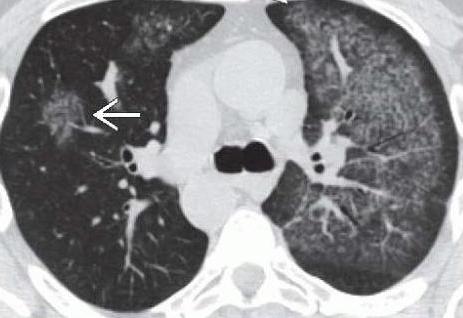

- Рак легкого. Эта патология распространена среди курящих людей пожилого возраста. В большинстве случаев рак диагностируют у мужчин.

При раке легкого кровотечение свидетельствует о распаде опухоли и повреждении сосудов. Остановить его бывает очень сложно. Особо опасно профузное кровотечение, при котором выделяется 500 мл биологической жидкости. Подобный симптом может закончиться летальным исходом. Помимо того что идет кровь изо рта, пациенты жалуются на затруднение дыхания, кашель, потерю веса.

Кровотечение при раке легких: особенности

Рак легкого считается одной из самых распространенных онкологических патологий среди мужчин. В большинстве случаев он развивается на фоне хронических воспалительных болезней дыхательной системы. Главным фактором риска считается злоупотребление табакокурением на протяжении долгих лет. Источником кровотечения при раке являются поврежденные сосуды или сама опухоль, находящаяся в фазе распада.

Признаками заболевания является длительный сухой кашель, не поддающийся лечению. Через несколько месяцев присоединяется кровохарканье. Помимо этого отмечается лихорадка, выраженная слабость, одышка и потеря веса. Кровотечение может иметь различный объем: от малого (50-100 мл) до профузного (более 0,5 литра). В большинстве случаев оно сопровождается кашлем. При этом имеется высокий риск аспирации и развития геморрагического шока.